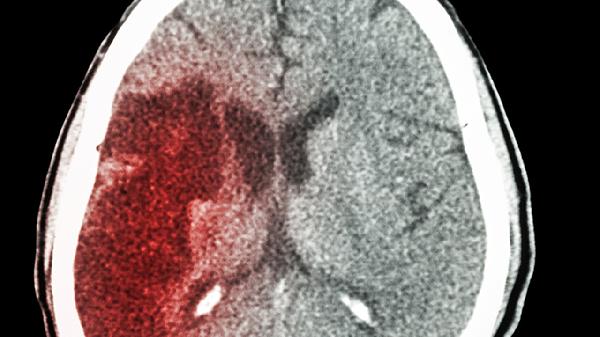

脑梗后焦虑的日常护理需保持规律作息,每天保证7-8小时睡眠,午休不超过30分钟。饮食选择富含色氨酸的小米、香蕉等食物,限制咖啡因摄入。每周进行3次以上舒缓运动如八段锦,避免剧烈活动诱发血压波动。建议家属陪同参与社区康复活动,逐步重建社交圈。定期复查头颅CT评估脑部恢复情况,若出现持续情绪失控需及时复诊调整治疗方案。